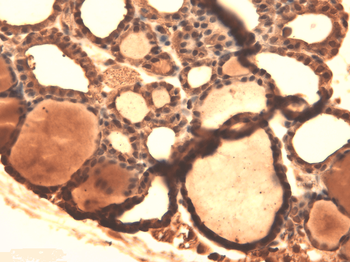

IHC-P image of mouse ovary tissue using NIS antibody (2.5 ug/ml)